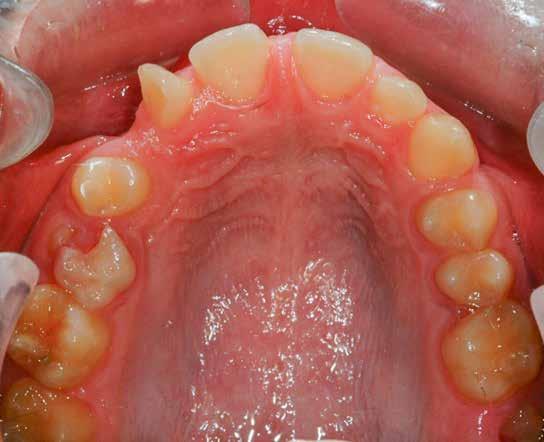

Lány páciensem I. fázisú kezelését 10 évesen kezdtük el bimaxilláris funkciós, kivehető készülékkel. Megfigyelhetőek a class 2-es eltérésnél tipikusan jellemző szűk felső és alsó fo-

gívek, valamint a nagy overjet, a mandibula disztál helyzete, továbbá a felső metszőfogak protrúziója, amelynek kialakulásához sokszor hozzájárul az ujjszopás is (1-3. képek)

A vegyes fogazati kezelési célok a fogívek tágítása és a mandibula meziális irányú növekedésének a biztosítása volt. Fontos, hogy az ilyen típusú készülékeket nem csak éjszaka, hanem napközben is – amennyit csak lehet – hordani kell a minél hatékonyabb működés érdekében. A 18 hónapos első fázisú kezelésnek köszönhetően az alap kezelési célok megvalósultak, sikerült a class 1-es okklúziót beállítani (4-7. képek).

Abban az esetben, amikor az első fázisú kezelési célok elérése megtörtént, de még nem törtek elő a maradó fogak az első moláristól az első molárisig – mintegy passzívan, csak éjszakánként hordva –, tovább folytatjuk a funkcionális kivehető készülék viselését.

Esetünkben 18 hónap után a maradó fogazat előtörése megtörtént, így rögtön folytathattuk a fogszabályozást.

A második fázisú kezelés Pitts-21-es fix fogszabályozó készülék alkalmazásával történt meg. A Pitts elveknek megfelelően a kezelési célok a felső középső metszőfogak megfelelő pozicionálása, a 12 fogas (6-ostól – 6-osig) mosoly, az ideális íves lefutású mosolyvonal kialakítása, továbbá az okklúzió finomítása voltak. Mint mindig, a felső fogíven mosolyvonal beállító esztétikai pozicionálást (Smile Arc Protection - SAP) alkalmaztunk, a mes-

terséges harapásemelés pedig az alsó hatosokra, majd később a felső négyesekre került (8. kép). Az intermaxilláris elasztikus gumihúzás class-2-ess vektorú volt annak érdekében, hogy a disztálharapás korrekciója tökéletes legyen (9. kép). A harapást beállító elasztikus gumihúzásokat – mint minden kezelésnél –, ebben az esetben is folyamatosan, az egész kezelés alatt 24 órában (étkezések kivételével) viselte páciensünk.

A második Pitts-21 fix készülékes fázis ideje 16 hónap volt (10-12. képek)

A fogszabályozás aktív fázisa után minden kezelésnél a retenció, a passzív helyben tartó fázis a kezelési eredmény megtartására rendkívül fontos!

Az Essix retainerek, az egy fogívre kiterjedő mélyhúzott sínek, valamint a felső és alsó frontfogakra orálisan ragasztott fix retainerek mellett, a harapás sagittális rögzítésében elengedhetetlen szerepe van az ún. Pitts Izom Tréning Splint-nek, amelybe a páciens élharapásban összeharap, így az megakadályozza az alsó fogsor visszamozdulását a disztálharapásos helyzetbe (13. kép)